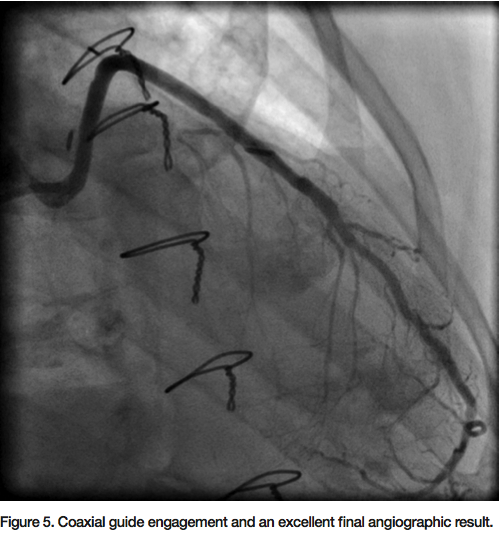

90% eccentric focal stenosis in the distal portion of the vein graft, very close to the anastomosis (Figure 2). Weight-based bivalirudin was initiated and a 6 Fr AL1 guide was used to cannulate the SVG to LAD. Though the severe tortuosity caused the cannulation of the graft to be challenging, a very co-axial supportive guide position was achieved (Figure 3, Figure 5). The lesion was crossed with a Kinetix wire (Boston Scientific). Due to the proximity of the lesion to the anastomosis, no distal protection device was deployed. A 3.5mm x 12mm Resolute drug eluting

stent (DES) (Medtronic) was deployed at high pressure directly to the lesion without pre-dilation (Figure 4). Repeat angiogram confirmed successful deployment of the stent with a TIMI-3 flow and no residual stenosis (Figure 5). The guide and sheath were removed and a hemostatic wrist compression device was applied for 2 hours. The patient tolerated the procedure well. There was no post-procedure increase in the cardiac enzymes and he was discharged home the next day.